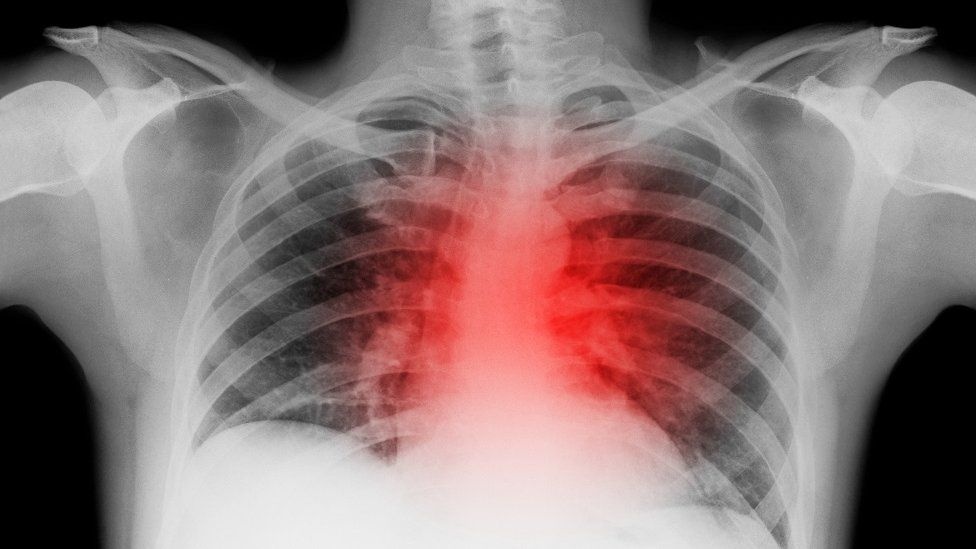

Nghiên cứu mới phát hiện ngay cả những người bị Covid-19 nhẹ cũng có nguy cơ đau tim, đột quỵ cao hơn. Ảnh: Shutter Stock.

Nghiên cứu mới cho thấy ngay cả người nhiễm nCoV nhẹ cũng có nguy cơ bị đau tim, đột quỵ cao hơn. Điều này dấy lên mối lo về đại dịch bệnh tim mạch ở những người khỏi Covid-19.

Một báo cáo gần đây được công bố trên tạp chí Nature Medicine, cho thấy ngay cả người mắc Covid-19 thể nhẹ cũng làm tăng nguy cơ lâu dài mắc các bệnh tim mạch nghiêm trọng như đột quỵ, đau tim và suy tim. Nghiên cứu nhấn mạnh những hiểu biết hạn chế của chúng ta về hậu quả mà Covid-19 cũng như tác động lâu dài mà đại dịch gây ra.

Từ 30 ngày đến một năm sau khi hồi phục Covid-19, những người khỏi bệnh có nguy cơ bị đột quỵ cao hơn 52%, nguy cơ đau tim cao hơn 63%, khả năng bị suy tim cao hơn 72%. Điều này có nghĩa trong hơn một năm, cứ 1.000 người bị Covid-19, thêm 5 người bị đột quỵ, 3 ca đau tim và 12 trường hợp bị suy tim. Ngoài ra, một số bằng chứng cho thấy nguy cơ hình thành cục máu đông nghiêm trọng trên phổi cũng cao hơn ở người khỏi Covid-19.

Một phát hiện gây chú ý đặc biệt là ngay cả những người bị bệnh nhẹ, nguy cơ bị đau tim, đột quỵ cũng cao hơn. Rủi ro đó không bị giới hạn về tiền sử bệnh lý mà có thể ảnh hưởng tới bất kỳ ai.